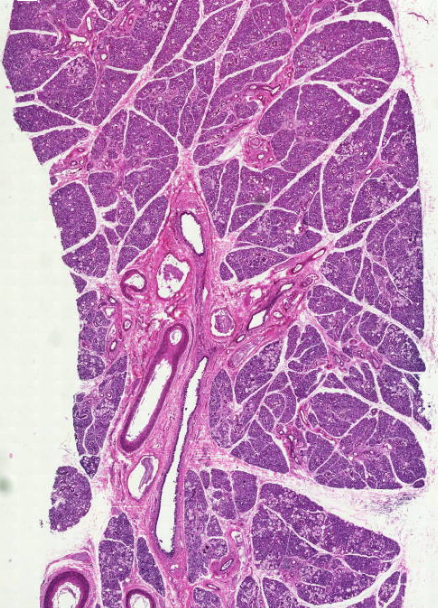

Поперечнополосатая мускулатура, Рыхлая волокнистая ткань

Skeletal muscles, loose areolar connective tissue

ماهیچه اسکلتی/بافت پیوندی سست